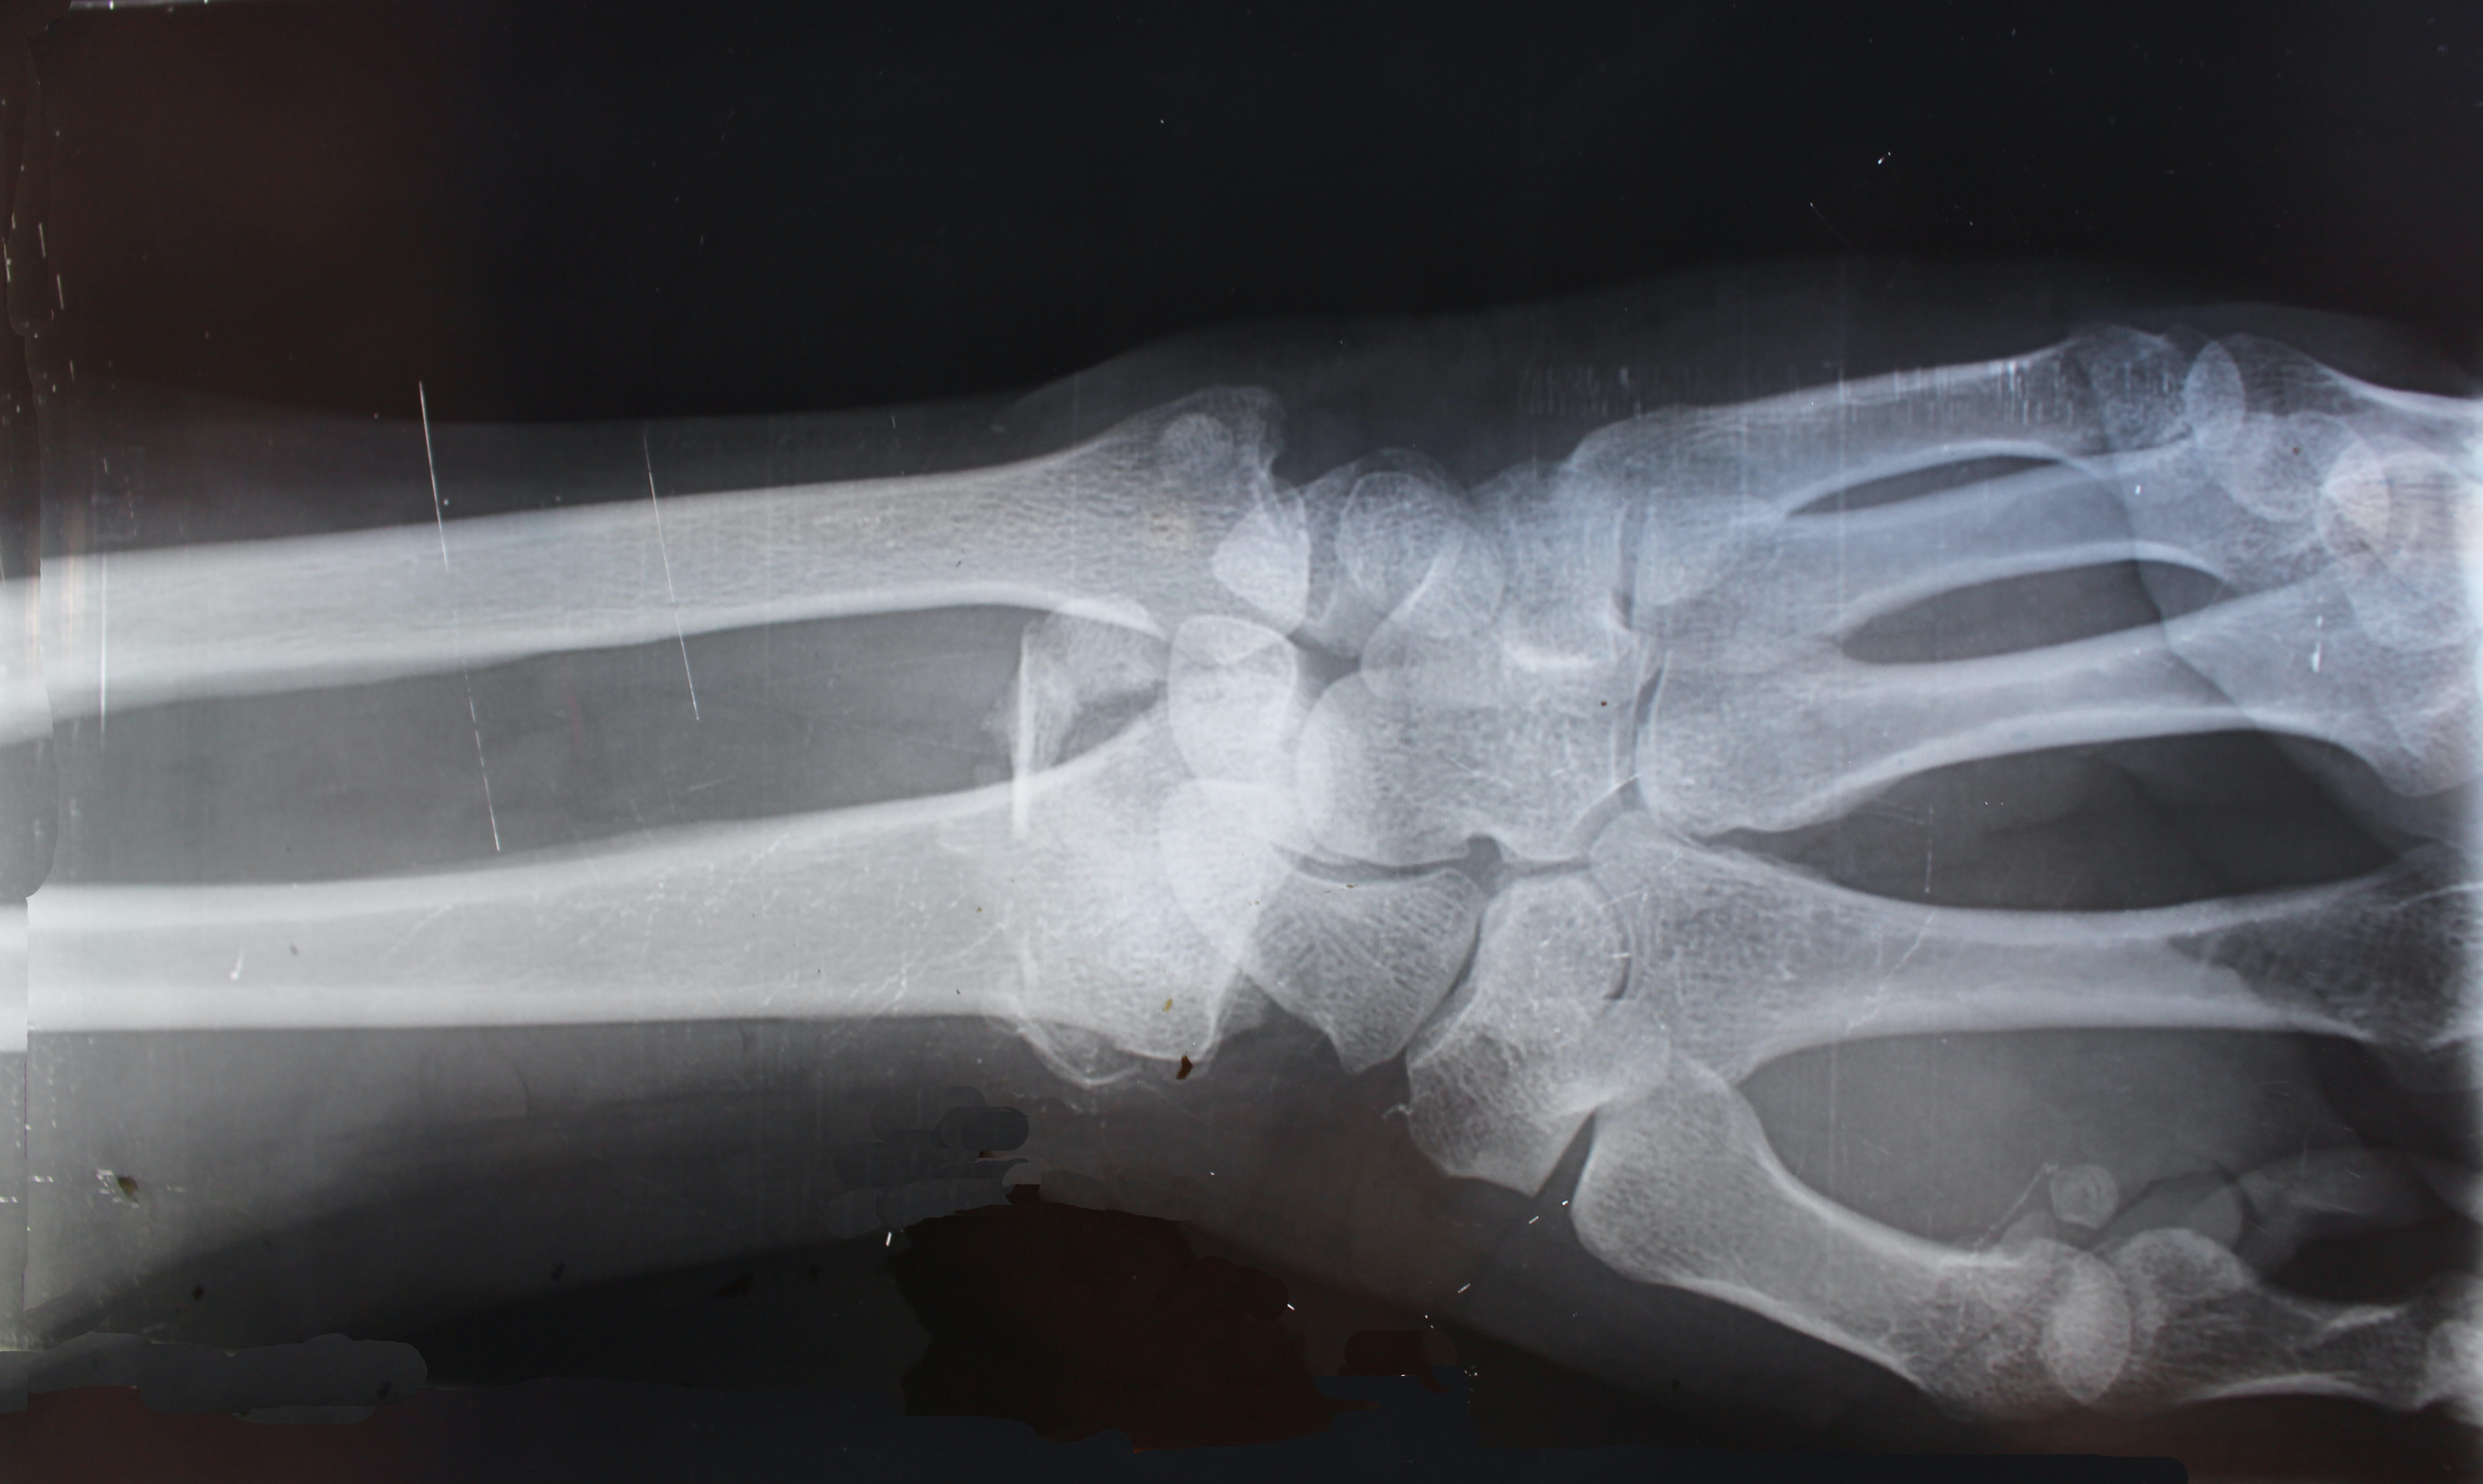

골관절염은 수일 통증이 느껴지는 경우 정형외과 엑스레이 촬영으로 쉽게 진단받을 수 있습니다. 엑스레이에서 확인이 되더라고 다른 질환으로 인해 증상이 유발된 것은 아닌지 확인이 필요합니다. 이러한 경우 관절에 찬 물을 추출해 검사하거나 피 검사를 진행하기도 합니다.